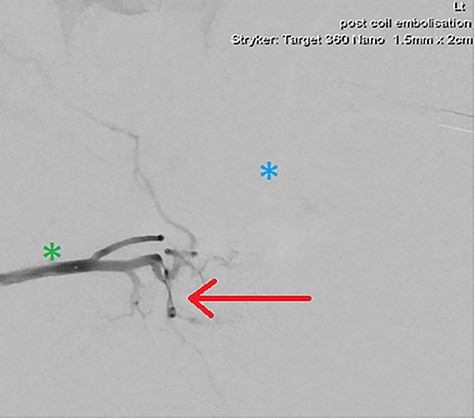

Heparin (3000 IU) was provided. Given contralateral feeding vessels, the right CFA was cannulated with the aforementioned steps mirrored, placing a microcatheter in the pseudoaneurysm via the left IPA. Two Target Neurovascular Microcoils (Stryker) were deployed at the pseudoaneurysm neck, with bilateral microcatheter angiography confirming satisfactory occlusion (Figs 4 and 5). All devices were removed, with Proglide (Abbott) arterial closure.

DSA demonstrating significantly reduced flow into the cavernosal artery pseudoaneurysm post-coil embolization (red arrow); note the left (blue asterix) and right (green asterix) distal branches of bilateral internal pudendal arteries for reference.

Final intraoperative fluoroscopic image demonstrating microcoil placement (red arrow); note the microcatheter placement within the left (blue asterix) and right (green asterix) distal branches of bilateral internal pudendal arteries for reference